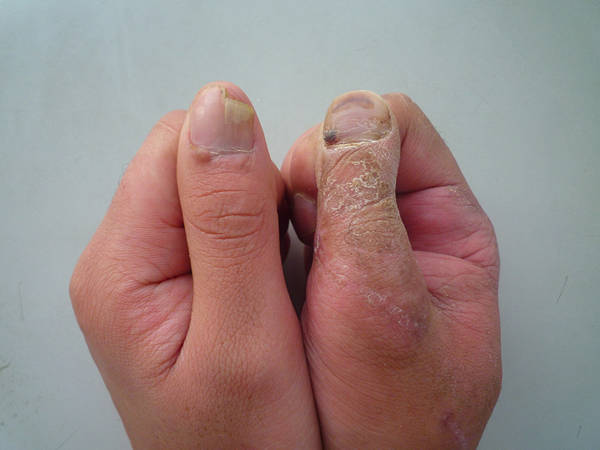

[手指再造] 拇再造术后供区的另一种修复(12.23随访照片来了)

1.jpg 2.jpg 3.jpg 4.jpg 5.jpg 6.jpg 7.jpg 8.jpg 9.jpg 10.jpg 11.jpg 12.jpg 13.jpg

功能和外观都很好,学习了,池主任的病人应该感到幸运和幸福